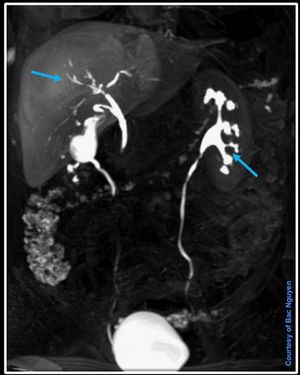

Liver Spesifict Contrast Agent Primovist/Eovist @ Siemens 3T Prisma Dual elimination approx. 50% renal system and 50% hepatobiliary system.#Siemens_MRI #siemens #mri #primovist #gadolinium